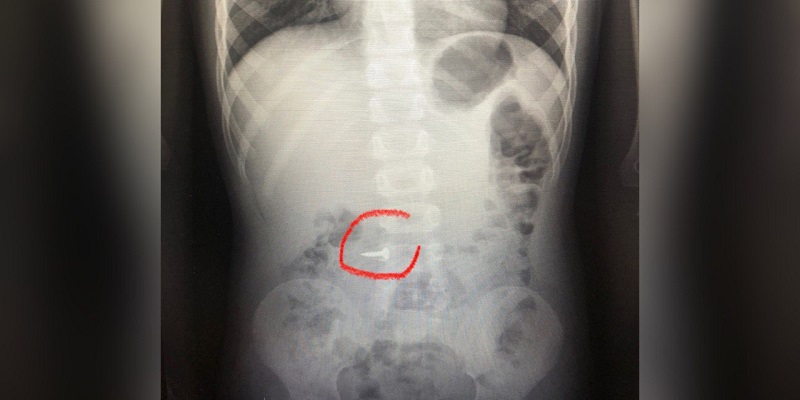

Врачи 2-й детской областной больницы в Воронеже продемонстрировали снимки. На одном из рентгеновских снимков можно видеть крепёжный элемент, который оказался в желудке ребёнка после того, как тот его нечаянно проглотил во время игры.

Медики отмечают, что в большинстве таких случаев приходится использовать хирургическое вмешательство. И чтобы подобного в детьми не происходило, рекомендуется не только осуществлять надлежащий присмотр, но и рассказывать о том, что проглатывание несъедобных вещей может привести к самих тяжёлым для организма последствиям.